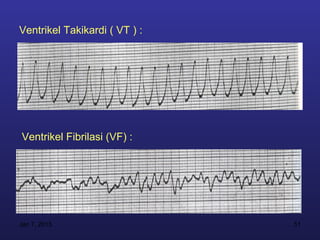

Ventrikel Takikardi ( VT ) :

Ventrikel Fibrilasi (VF) :

Ventrikel Takikardi (VT ) : Ventrikel Fibrilasi (VF) : Jan 7, 2013 51